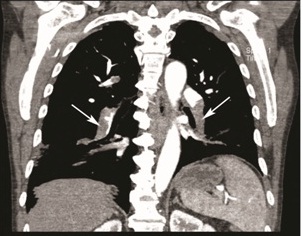

The chest X-ray (CXR) showed a normal cardiomediastinal silhouette with clear lungs with no pneumothorax or pleural effusion. A non-contrast CT of the head showed no active disease. Laboratory testing was significant for an elevated D-dimer but normal troponin level. Subsequent CT angiogram of the thorax showed large filling defects within the right main pulmonary artery, upper, middle and basilar segments. Additional filling defects were present within the left descending pulmonary artery and all of the basilar segments consistent with bilateral multifocal pulmonary emboli [Table/Fig-3a, b]. A wedge-shaped peripheral consolidation in the lateral basal segment of the right lower lobes suggested pulmonary infarcts. Incidentally, a moderate-sized hemangioma within the T12 vertebral body was noted. He was started on a therapeutic intravenous heparin drip for treatment of PE and admitted to the telemetry unit for serial cardiac enzymes.

Coronal section of CT chest showing filling defects bilaterally (solid white arrow).

Transverse section of CT chest showing filling defects in the right pulmonary artery (solid white arrow)